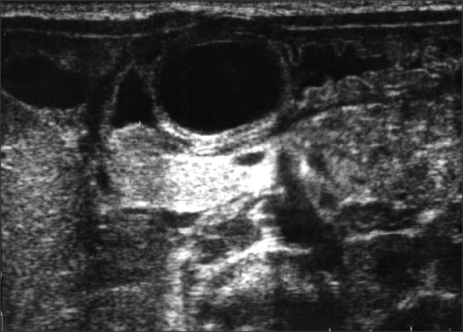

A 3-day-old girl, born by normal vaginal delivery at 38 weeks gestation with a birth weight of 2,718 g, presented with 2 days of non-bilious vomiting and feeding difficulties since birth. A routine prenatal ultrasonography performed at 31 weeks of gestation showed a gastric bubble sign. Repeat ultrasonography at 34 weeks of gestation showed that the gastric bubble sign had disappeared. On presentation, the patient was severely dehydrated and weighed only 2,436 g. Her abdomen was distended. An olive-like mass was palpable in the upper abdomen following insertion of a nasogastric tube. Laboratory test results revealed electrolyte disturbances consistent with severe hypovolemia and alkalosis. There were no vertebral anomalies identified. Plain abdominal radiography demonstrated a distended stomach with no gas distal to the stomach—findings consistent with gastric outlet obstruction. Ultrasonography revealed an “intraluminal” cyst arising from the pyloric orifice and virtually obliterating it (

Fig. 1). The wall of the lesion had a hypoechoic outer rim and a thick echogenic inner rim or gastrointestinal signature [

Fig. 1“Intraluminal” cyst arising from the pyloric orifice seen on ultrasonography. The wall of the lesion had a hypoechoic outer rim and a thick echogenic inner rim or gastrointestinal signature and the lumen was hypoechoic.